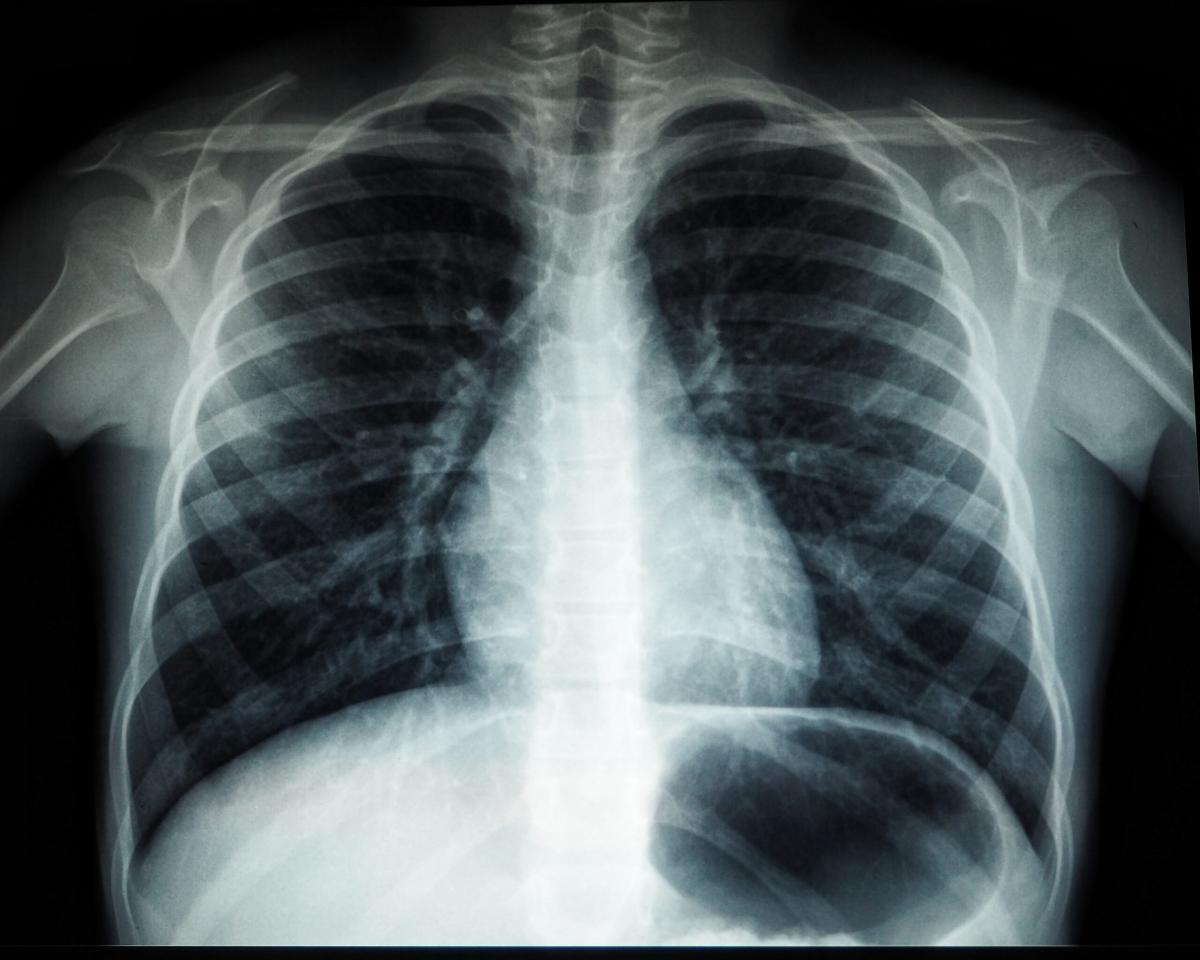

Urządzenie to posiada niezwykle wąski korpus, mierzący jedynie 58 cm. To z kolei pozwala przemieszczać go swobodnie przez drzwi czy bardzo wąskie korytarze. Najważniejsze jest jednak to, że niewielkie rozmiary aparatu w żaden sposób nie wpływają na wygodę jego używania czy jakość uzyskanego obrazu. W tym przypadku dostajemy do dyspozycji pięcioosiowy zakres zmiany położenia lampy. Ponadto jest to urządzenie niezwykle ergonomiczne bazujące na najnowocześniejszych technologiach, co pozwala uzyskać świetnej jakości obraz w wygodny i szybki sposób, przy zachowaniu minimalnej dawki promieniowania rentgenowskiego.

Kompaktowe rozmiary, jakimi charakteryzuje się mobilny aparat rentgenowski, wpływają nie tylko na jego proste przemieszczanie, ale umożliwiają równie jego ustawienie w małych i ciasnych pomieszczeniach. Z tego też powodu jest to aparat RTG, który świetnie sprawdzi się w różnego rodzaju gabinetach prywatnych czy mniejszych klinikach. Co wcale nie znaczy, że nie jest to dobre rozwiązanie dla dużych klinik czy szpitali. Tam również mobilny aparat RTG może stanowić doskonałe wyposażenie medyczne, które pozwoli na wygodne badanie pacjentów przy łóżkach.